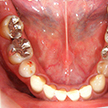

2. 初診時上顎面観

全顎パノラマ写真においては右上1番が失活歯、2番は叢生のままで不適合な前装冠(差し歯)、八重歯の3番は健全歯、4,5番も2番同様不適合冠処置となっています。比較的プラークコントロール(以下PCR)の良好な(歯ブラシの仕方が上手な)この患者様も同部が上手に磨けず不潔となり崩壊過程にあることが考えられます。

3. 初診時上顎